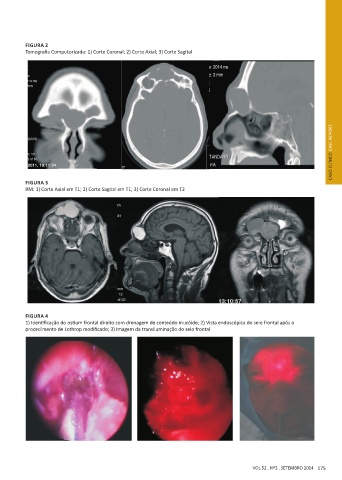

FIGURA 2

Tomografia Computorizada: 1) Corte Coronal; 2) Corte Axial; 3) Corte Sagital

FIGURA 3

RM: 1) Corte Axial em T1; 2) Corte Sagital em T1; 3) Corte Coronal em T2

FIGURA 4

1) Identificação do ostium frontal direito com drenagem de conteúdo mucóide; 2) Vista endoscópica do seio frontal após o

procedimento de Lothrop modificado; 3) Imagem da transiluminação do seio frontal